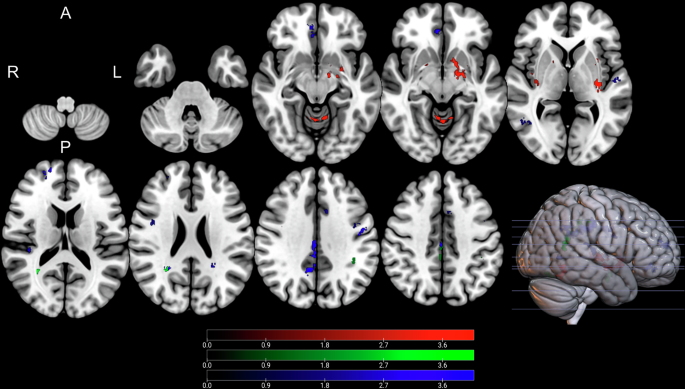

Whole brain analysis of NODDI parameters indicated that both ODI and NDI were significantly correlated with changes in postoperative UPDRS part III scores. These findings are illustrated in Supplementary Tables 2 and 3 as well as Figs. 2 and 3 (ODI) and Supplementary Figs. 3 and 4 (NDI values). Higher ODI values in the left pallidum, bilateral putamen, and bilateral insular cortex were associated with greater change in postoperative motor symptoms (P1-6, CWP: <0.001–0.038, Fig. 2). Conversely, negative associations were exclusively observed in white matter regions adjacent to the left middle frontal gyrus, left cingulate gyrus, and left precuneus (N1-3, CWP: <0.001-0.019, Fig. 3). Furthermore, higher ODI and NDI values in the bilateral insular cortex were related to a greater reduction in postoperative motor symptoms (ODI: P3, P5, CWP: <0.001-.003; NDI: P1–P3, CWP: <0.001–0.032). Additionally, increased NDI values in the left putamen were liked to greater reduction in postoperative motor symptoms (P1, CWP: <0.001). Negative associations between NDI and postoperative motor symptoms were identified in white matter regions adjacent to the left middle frontal gyrus, left precentral gyrus, right precuneus, and left paracingulate gyrus, corresponding to the previously mentioned negative ODI-clusters (N1-3, CWP: <0.001−0.019).

Clusters with a positive association between PD patients’ ODI-values and postoperative change in UPDRS (red), time spent in ON (green), and time spent in OFF (blue), as revealed by the whole brain analysis. Clusterwise P-values were corrected for multiple comparisons using a permutation-based approach and shown as the negative decadic logarithm of the p-value.